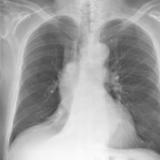

RLL Collapse 1 PA

Date: 02/28/2004

Views: 3442